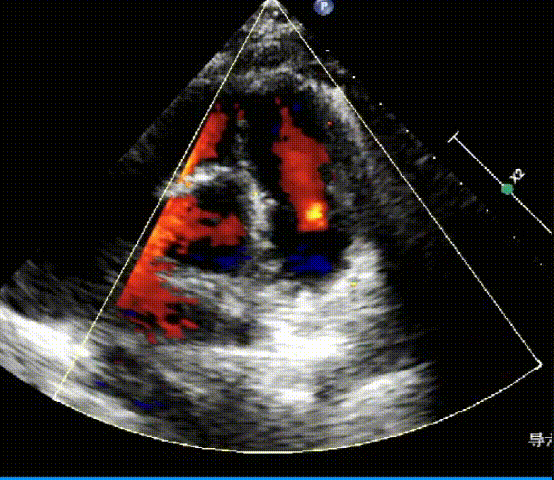

术后心脏超声

人工肺动脉瓣位置及功能正常,无明显关闭不全及瓣周漏。

经导管肺动脉瓣置换术取得圆满成功。